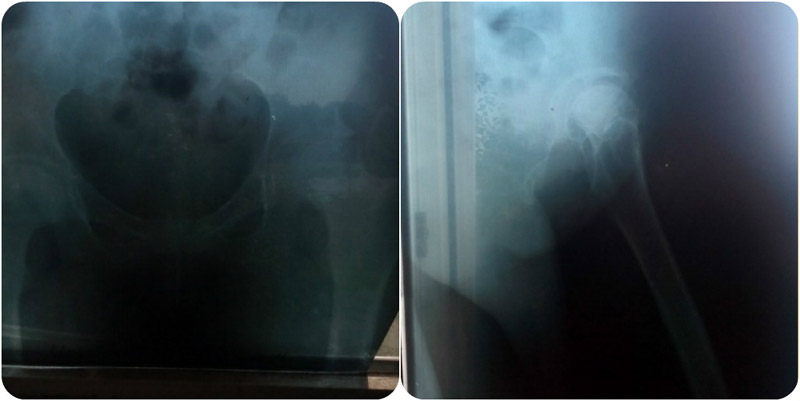

Елена вот уже два года борется с диагнозом: асептический некроз тазобедренного сустава.

Боль в ногах не покидает ее все это время. Передвигаться она вынуждена с помощью палочки. Но, несмотря ни на что, она два года искала всевозможные варианты предотвратить в дальнейшем разрушение сустава и начать жить полноценной жизнью 24-летней девушки. Оббивши все пороги чиновников, поликлиник удача повернулась к ней лицом – Елене согласились установить бесплатно импортный сустав. Но и тут девушка столкнулась с препятствием – нужны средства на медикаменты и доноры. На этой неделе Лене назначена операция, но средств на приобретение лекарств у девушки нет! По словам врачей на закупку потребуется около 6 тысяч гривен. А 10 доноров нужно найти до конца июля. Времени совсем нет! Операцию перенести не могут, так как в дальнейшем отделение закрывают на ремонт, а терпеть боль Лена уже не в силах…